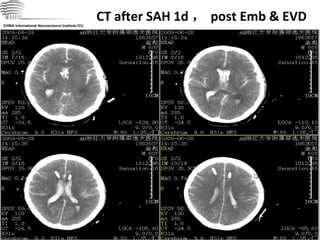

CT after SAH 1d , post Emb & EVD CHINA International Neuroscience Institute ICU

CT after SAH1d , post Emb & EVD CHINA International Neuroscience Institute ICU